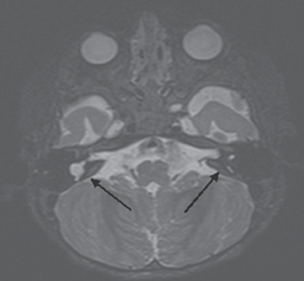

В связи с выявленными на КТ изменениями височных костей было принято решение о проведении дополнительного МРТ головного мозга и внутреннего уха (рис. 2).

По его результатам с двух сторон были выявлены МР-признаки рудиментарных улиток с частично сформированными полукружными каналами, с наличием асимметрии внутренних слуховых проходов. С двух сторон отмечалось и наличие вестибуло-кохлеарных нервов, отходящих от ствола мозга. Однако на уровне пирамиды височных костей тканевая структура прослеживалась четче справа, чем слева. Учитывая эти результаты МРТ, было принято решение о проведении правосторонней кохлеарной имплантации (правое ухо).